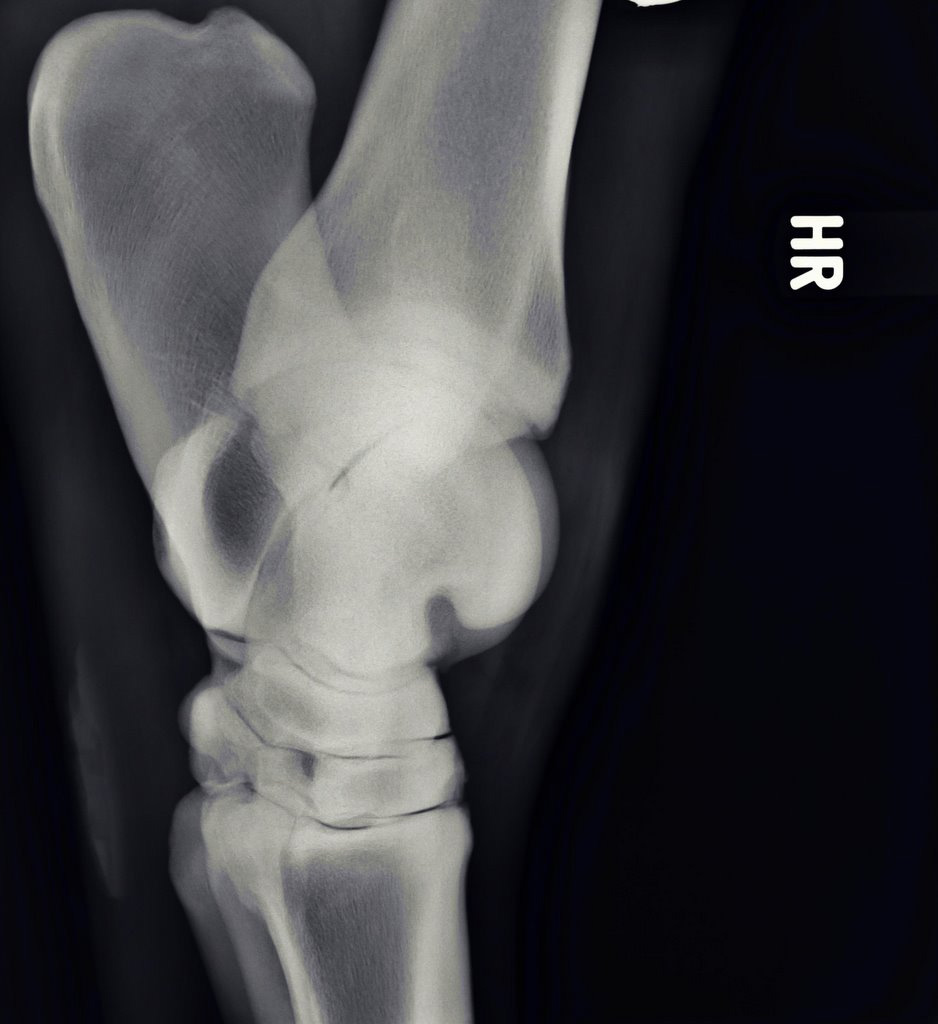

Illustrative Mindeststandardaufnahmen zur Beurteilung nach dem Röntgenleitfaden: